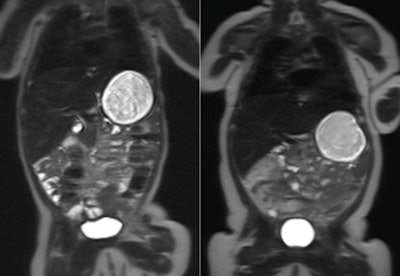

MRI scans of two babies at 10 weeks old. The child on the left was born to a healthy mother, while the child on the right was born to a mother with gestational diabetes. The white area on the outside of the body is fat tissue. Image credit: Imperial College London.

The babies wore special earmuffs to protect them from the noise of the scanner. Image credit: Lucinda Winckworth.Although babies born to mothers with gestational diabetes had no difference in body fat at birth when compared with those born to healthy mothers, at 2 months old, they had 16% more body fat than the control group.